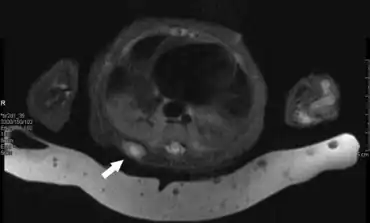

Hemithorax shows a soft tissue lesion

Based on their clinical presentation and gross appearance IMF tumors can be confused with a wide range of benign and malignant papular,nodular, and tumorous lesions particular in cases which involve multiple tumors. However, the presence of two zone histopathology, family history of disease, and presence of the above cited PDGFRB gene mutations are almost always definitive indicators of IMF. IMF and the classic form of mesoblastic nephroma have been suggested to be the same disease because of their very similar histopathology. However, mesoblastic nephroma tumor cells, unlike IMF tumor cells, express cyclin D1 and Beta-catenin proteins and therefore likely have a very different cellular origin than IMF tumors.[21][22] Infantile digital fibromatosis, a tumor that develops primarily in the fingers and toes, had been regarded as a type of IMF. However its tumors have a distinctly different clinical presentation and histopathology than IMF.[23] The World Health Organization (2020) redefined infantile digital fibromatosis as a benign tumor in the in the category of benign fibroblastic and myofibroblastic tumors and therefore different than IMF.[24]